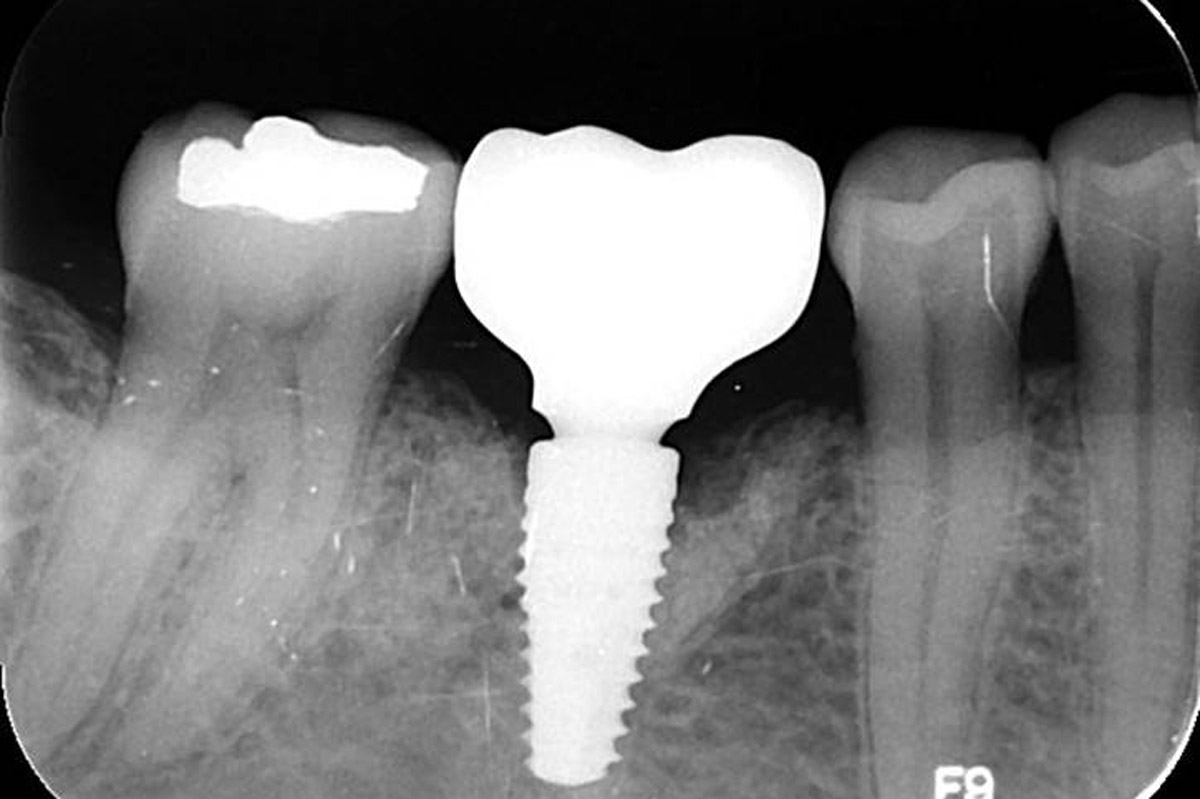

12/19 - Control X-Ray of the placed implant

Immediate implant placement using maxresorb® - Dr. Alejandro Signorio